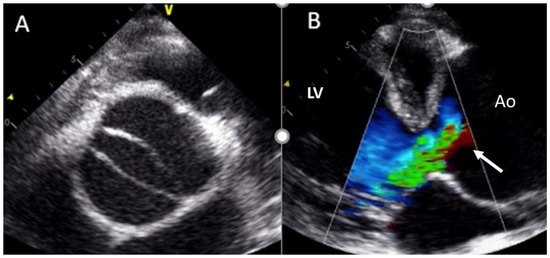

4.3. Aortic Regurgitation

- Although TTE is the technique of choice to identify valve morphotype, valve dysfunction, and ascending aorta dilation, CT and CMR improve the accuracy of aorta size measurement.